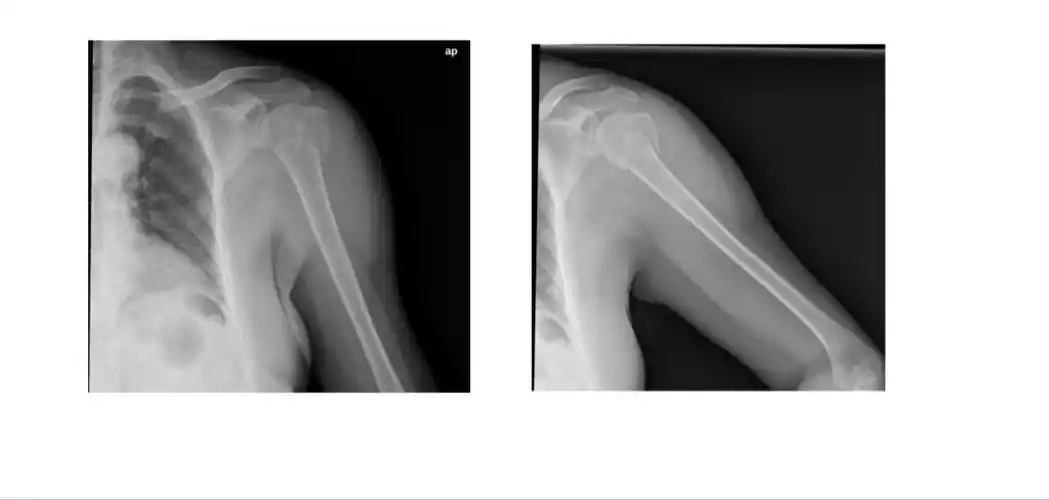

这是一例外翻嵌插的骨折,肱骨头的外翻单纯靠牵引是不能纠正的